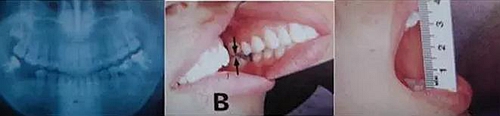

圖9. 上頜和下頜第二磨牙中發(fā)生的前方誘導(dǎo)干擾引發(fā)的張口困難。

下頜磨牙的遠(yuǎn)中頰側(cè)牙尖的近中頰側(cè)斜面和上頜磨牙的近中頰側(cè)牙尖的遠(yuǎn)中腭側(cè)斜面相接觸。

圖10. 不考慮下頜第三磨牙的咬合平面破壞的修復(fù)體制作完成后,

后方磨牙干擾引發(fā)的前方誘導(dǎo)干擾。